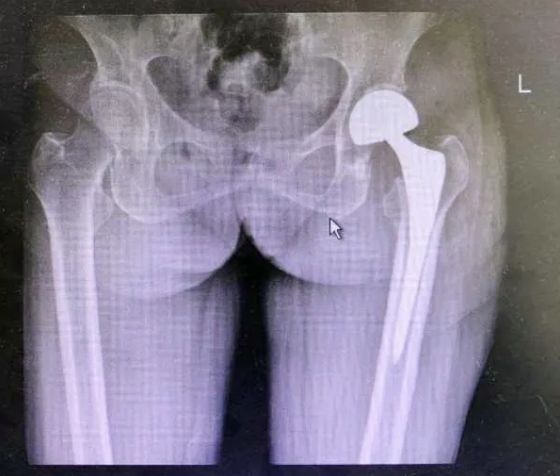

79岁的韩大娘在家不慎摔伤,左髋部疼痛于当地医院检查显示:股骨颈骨折(头下型),因子女在淄博工作生活,就诊于淄博市第四人民医院骨科,骨科二组副主任王宁接诊后为其完善各项辅助检查,考虑老人年龄及身体状况,组织手术麻醉科、内科等多个科室专家进行会诊,开展相关术前讨论,决定为老人实施股骨头置换术。手术顺利完成,术后,韩大娘在医护人员指导下进行相关功能锻炼,恢复效果显著。

目前,骨科二组已成功实施多例高龄且合并多种慢性老年疾病的人工股骨头置换手术,术后见效快,大大提高了患者的生活质量。

股骨颈骨折,按部位划分属于髋部骨折,是老年人摔倒后较常见的骨折类型,这个部位一旦发生骨折就意味着立刻失去了行走活动能力,且患者多数为老年人,因此髋部的骨折也常被称为人生最后一次骨折,保守治疗并发症多坠积性肺炎、褥疮、深静脉血栓都是能够危及病人生命的并发症,近年来人工关节置换在临床上得到应用,它具有内固定不能达到的效果。人工关节置换能在较短时间恢复患肢功能到损伤前的水平,减少卧床时间,术后3天便可下地行走,避免因长期卧床导致的肺部、尿路感染及深静脉血栓形成等并发症的发生,有利于改善心肺功能,提高病人生活质量,并且缩短了住院及康复时间,减轻了病人经济负担。